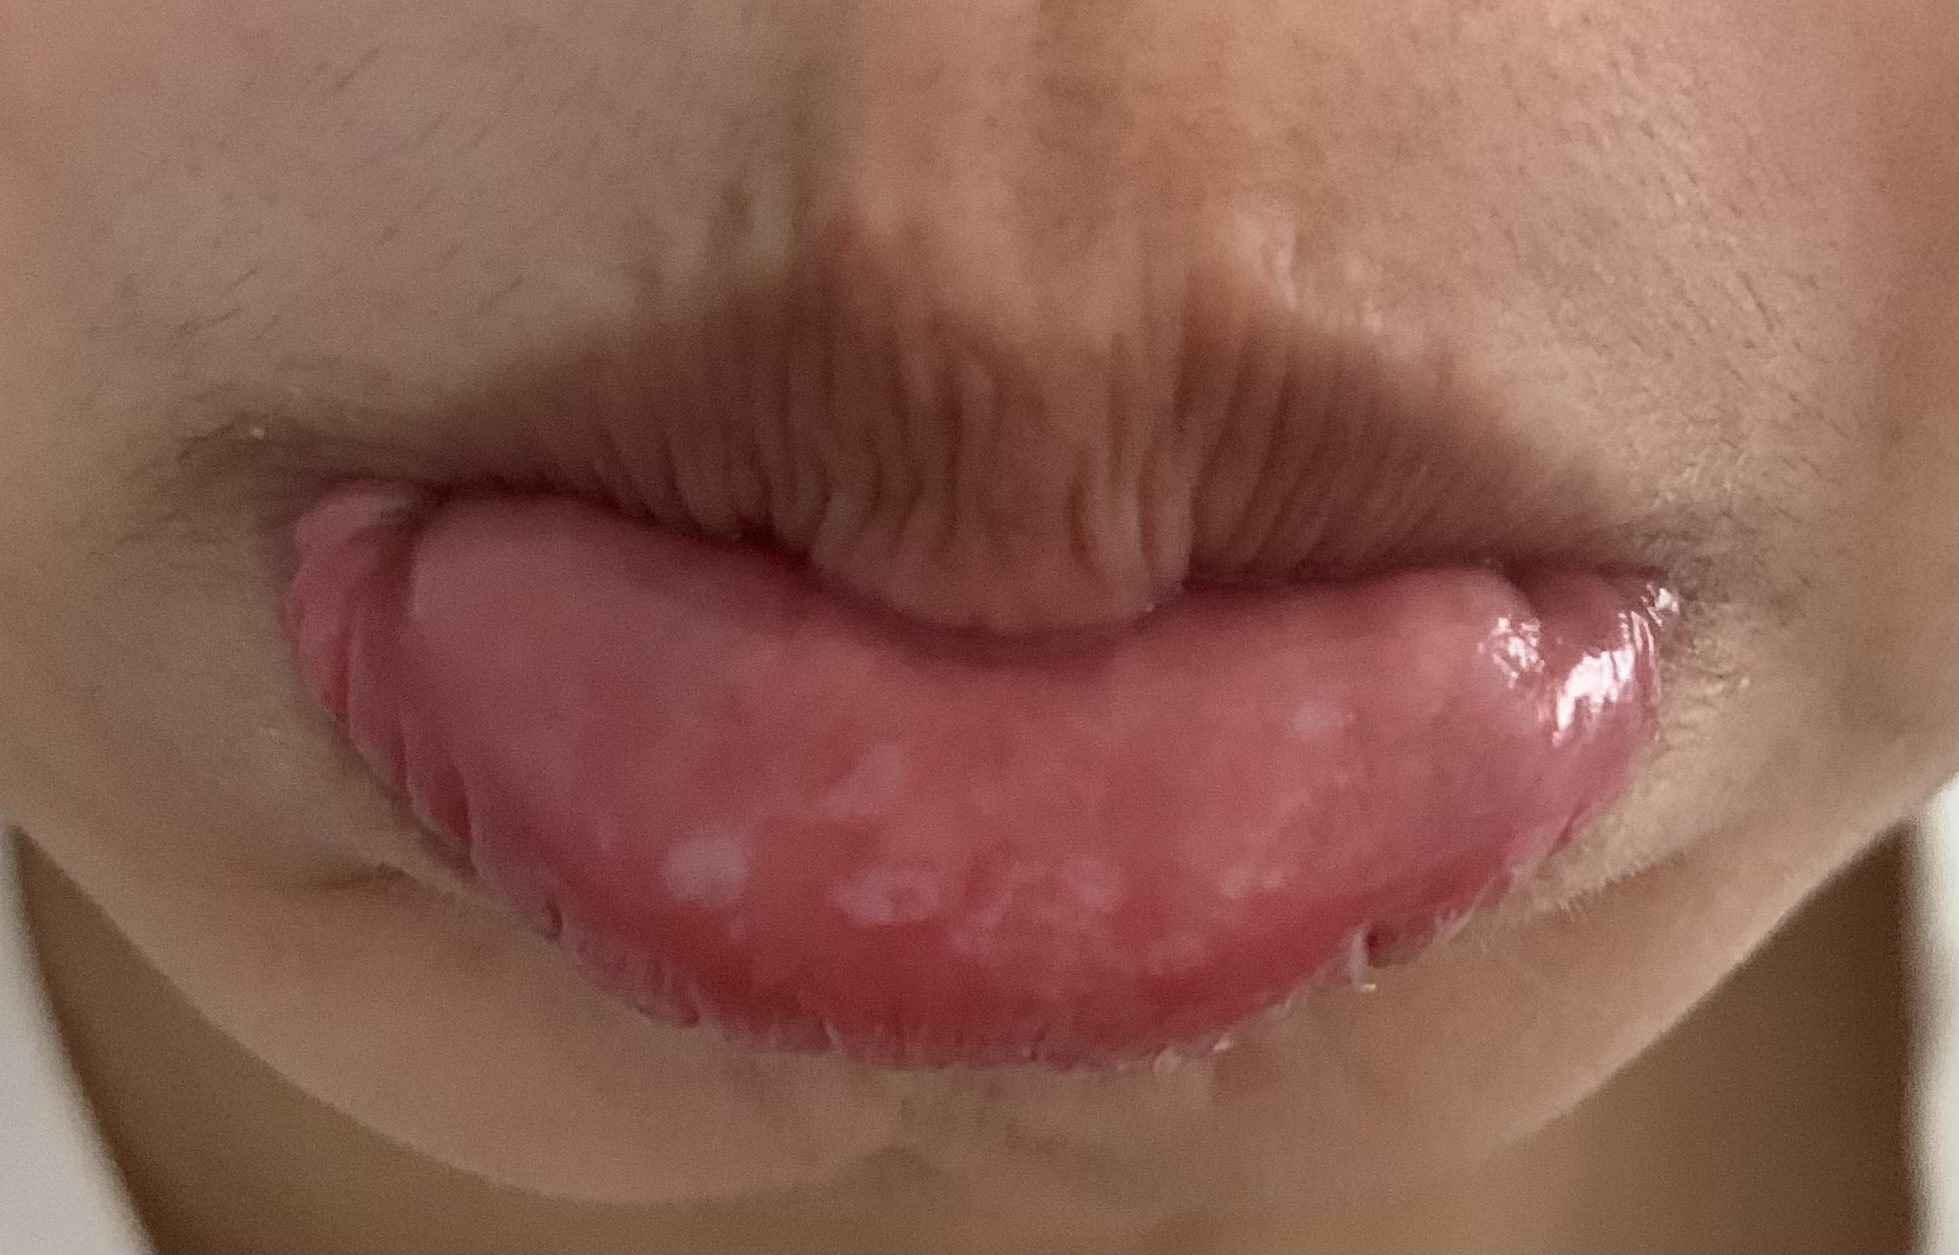

唇のブツブツ:フォアダイスの原因・治し方・予防等について - 美容外科船橋中央クリニック&青山セレスクリニック。

唇のブツブツ:フォアダイスの原因・治し方・予防等について - 美容外科船橋中央クリニック&青山セレスクリニック。

唇のブツブツ:フォアダイスの原因・治し方・予防等について - 美容外科船橋中央クリニック&青山セレスクリニック。

唇のブツブツ:フォアダイスの原因・治し方・予防等について - 美容外科船橋中央クリニック&青山セレスクリニック。